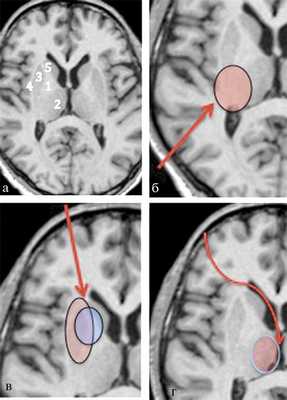

Рис. 2. Анатомо-топографическое обоснование используемых эндоскопических доступов c учетом анатомия базальных ядер. а — анатомия базальных ядер: 1 — внутренняя капсула (capsula interna); 2 —таламус (thalamus); 3 — чечевичное тело (nucleus lenticularis); 4 — наружная капсула (capsula externa); 5 — хвостатое ядро (nucleus caudatus). Анатомо-топографическое обоснование используемых эндоскопических доступов: б — при путаменально-таламических гематомах; в — при путаменальных и путаменально-капсулярных гематомах; г — при таламических гематомах с прорывом (для выполнения ЭТС и удаления крови из желудочковой системы). Стрелками указаны проекции эндоскопических доступов. Для точности установки портов использовалась система безрамной нейронавигации S7 «Medtronic». Таким образом, использовались три основных эндоскопических доступа: фронтальный, париетальный, прекоронарный (с одномоментным проведением ЭТС при ВЖК). При гематомах ЗЧЯ порт устанавливался в области от максимально короткой траектории до хирургической цели.